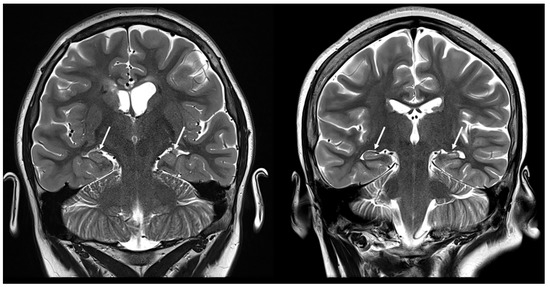

Incidence and Characteristics of Cerebellar Atrophy/Volume Loss in Children with Confirmed Diagnosis of Tuberous Sclerosis Complex

Mertiri, L.; Boltshauser, E.; Kralik, S.F.; Desai, N.K.; Lequin, M.H.; Huisman, T.A.G.M. Incidence and Characteristics of Cerebellar Atrophy/Volume Loss in Children with Confirmed Diagnosis of Tuberous Sclerosis Complex. Children 2024, 11, 627. https://doi.org/10.3390/children11060627